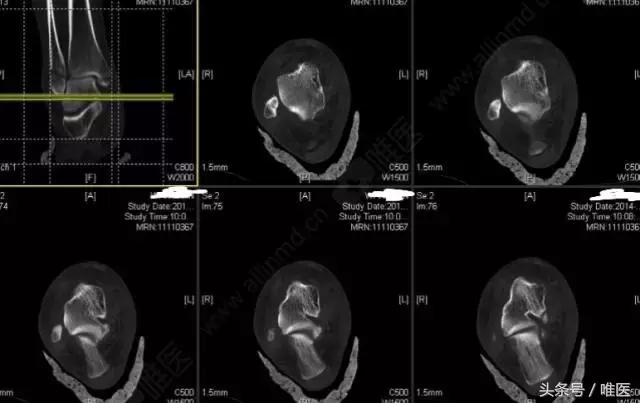

CT二维重建: 右侧踝关节骨折

治疗前影像